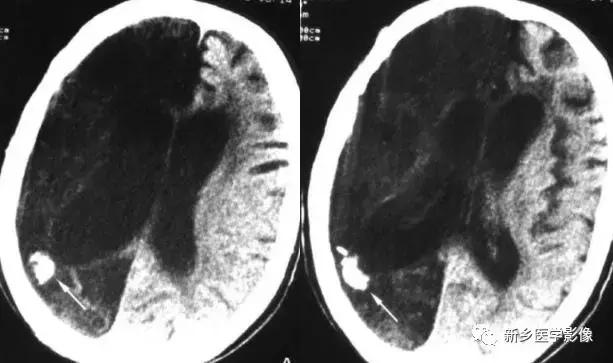

十五、外伤后颅内钙化

外伤后导致颅内钙化少见,主要见于慢性硬膜下血肿及硬膜外血肿,钙化多呈条状或环状,分布于原血肿部位,结合病史易于诊断。